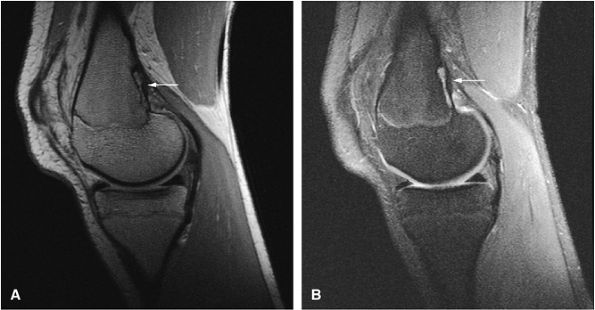

FIGURE 14-1 ● T1-weighted images (A) before and (B) after intravenous gadolinium administration show malignant fibrous histiocytoma. The tumor enhances after intravenous injection of gadolinium. Central tumor necrosis remains unenhanced (arrow).

Gadolinium has been used to enhance contrast on T1-weighted images to better characterize osseous and soft-tissue tumor involvement.2,7,15,22,23,24 On gadolinium-enhanced images, nonenhancing regions are thought to represent areas of nonviable tumor or necrosis (Fig. 14-1). Gadolinium-enhanced images may also be useful for differentiating peritumoral edema from underlying tumor and recurrent tumor from scar or fibrosis.25